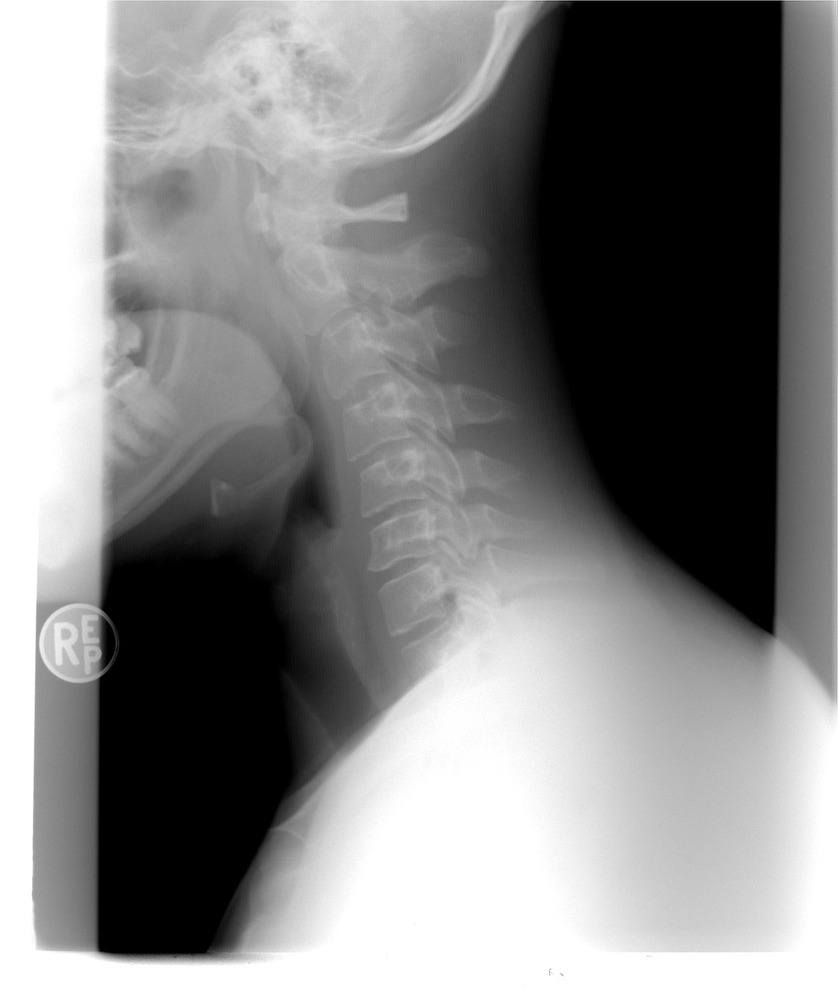

Røntgenundersøgelse